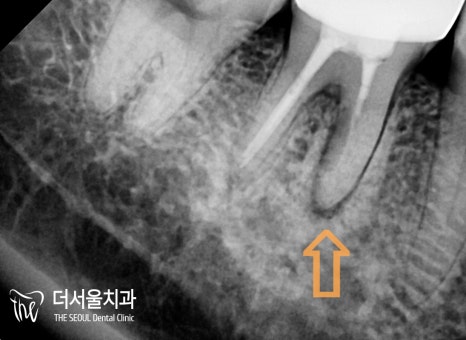

반갑습니다, 여러분! 더서울치과 박현준 원장입니다. 오늘 여러분들께 소개해 드릴 케이스는 제목 그대로, 아말감 밑으로 생긴 이차충치 에 대한 진료